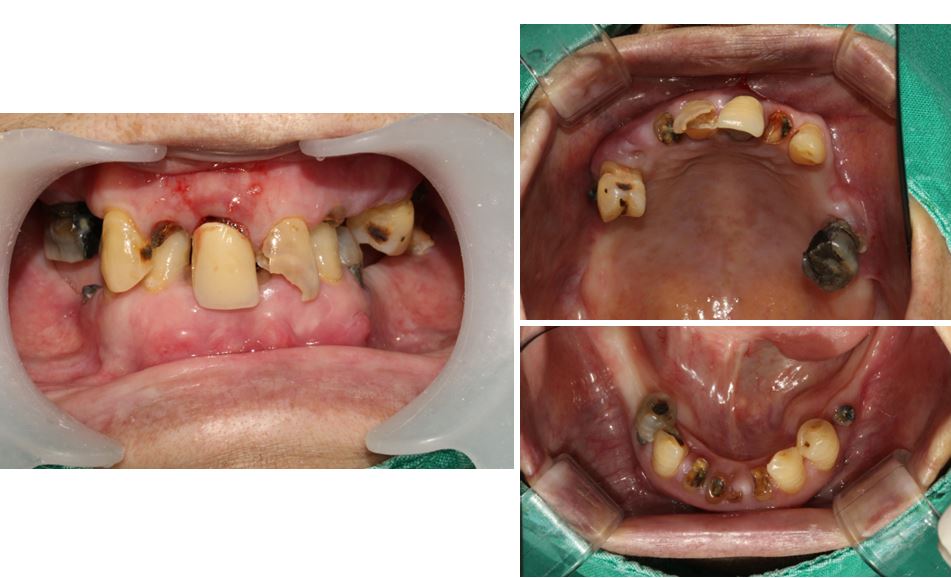

[초진 시 구강 상태]

• 모든 치아가 썩어서 파절되고, 교합이 맞지 않은 상태

• 음식물 섭취가 전혀 되고 있지 않은 상태 ( 이상태를 유지할 경우 위장관 문제로 이어질 수 있습니다.)

내원 당시 치아 상태

모든 치아가 썩어서 파절되고 교합이 없는 상태로 음식물 섭취가 전혀 되고 있지 않은 상태였습니다.